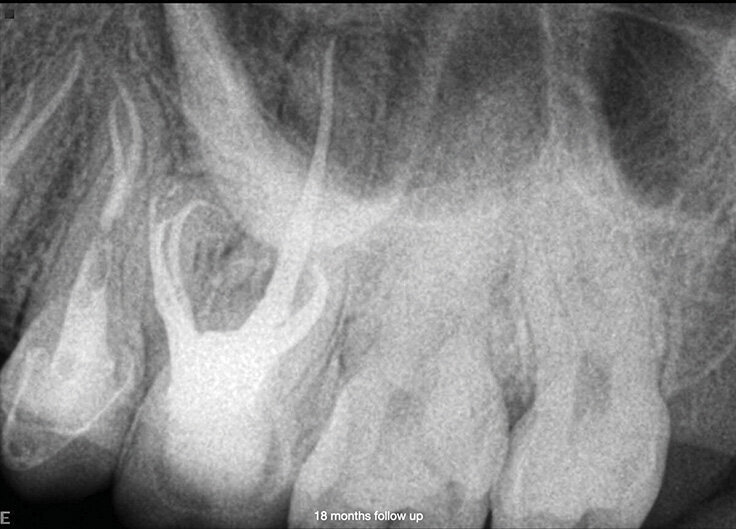

Slučaj 3 – Slika br. 10: Periapikalni kontrolni Rtg snimak nakon godinu dana od tretmana

Slučaj 3 – Slika br. 11: Periapikalni kontrolni Rtg snimak 18 meseci nakon tretmana

Poslednji slučaj o kome bih želeo da govorim u ovom članku, jedan je od najizazovnijih tretmana. Pacijentkinja je upućena iz inostranstva na remont gornjeg molara jer je insistirala na spasavanju zuba. Na malom rendgenskom snimku (Slika br. 6) sam jasno video da imamo separisan instrument u mezijalnom korenu, ali je anatomija bila veoma sumnjiva. Pacijentkinja mi je dala CD sa CBCT urađenim za nju, i gledajući različite delove , mada bih više voleo veću rezoluciju snimka (Slika br. 7), primetio sam 3 različita izlaza za mezijalni koren sa veoma neobičnom anatomijom. Proučavajući ovaj slučaj primetio sam i grananje na palatinalnom korenu u apikalnoj oblasti. Objasnio sam pacijentkinji da ću dati sve od sebe da joj spasem zub. Koristio sam istu sekvenca turpija Traverse i Zenflex u distalnom i palatalnom kanalu korena zuba do pune radne dužine, a kod mezijalnog korena sam dostigao do zalomlejnog instrumenta i prešao na veoma delikatan zadatak njegovog zaobilaženja i obrade ovog veoma složenog sistema korenskih kanala. Slika br. 8 prikazuje neposrednu postoperativnu i 3D obturaciju mezijalnog kompleksa, kao i palatinalno grananje. Slike br. 9 i 10 su nakon 12 i 18 meseci od tretmana gde se vidi dobro zarastanje i svaki put kada uzmem da pogledam iz drugačijeg ugla vidim složenost mezijalnog korena.